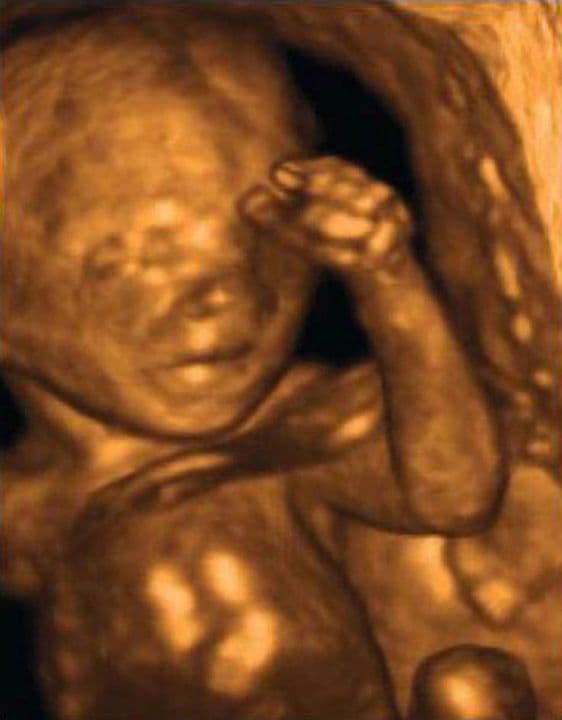

This image shows how much less obvious the soft spot on the top of the baby’s head has become by now. The fingers show up well here, and as your baby increases in size, it becomes easier and easier for ultrasound to show this level of detail.